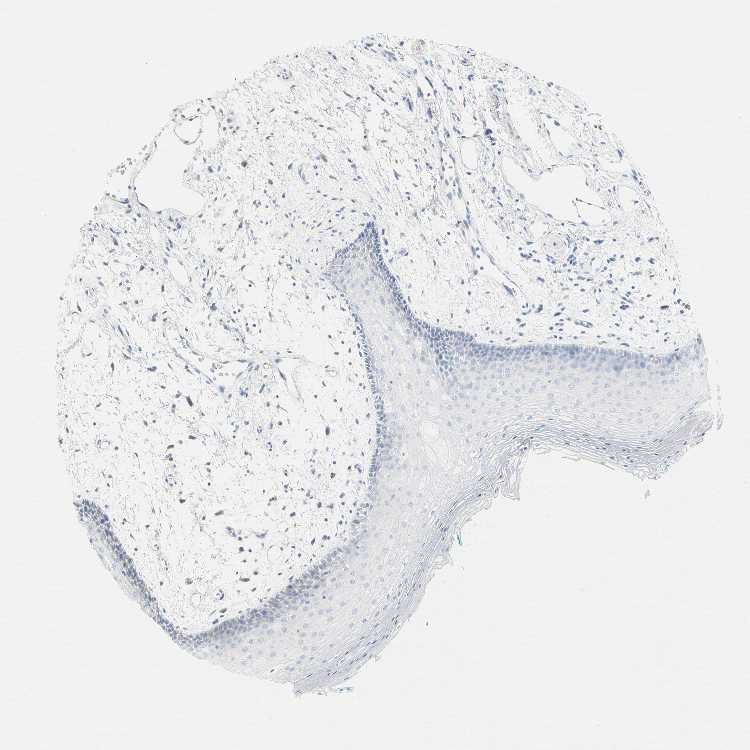

TISSUE PRIMARY DATA ORAL MUCOSA Show tissue menu

Oral mucosa

ORAL MUCOSA - Antibody stainingi

Antibody staining in the annotated cell types in the current human tissue is reported as not detected, low, medium, or high, based on conventional immunohistochemistry profiling in selected tissues. This score is based on the combination of the staining intensity and fraction of stained cells.

Each image is clickable and will lead to virtual microscopy that enables deeper exploration of all samples and also displays staining intensity scores, fraction scores and subcellular localization as well as patient and tissue information for each sample.

Antibody HPA039247Antibody HPA043684Antibody HPA063394Antibody CAB008686

Squamous epithelial cells HighLowMediumNot detected